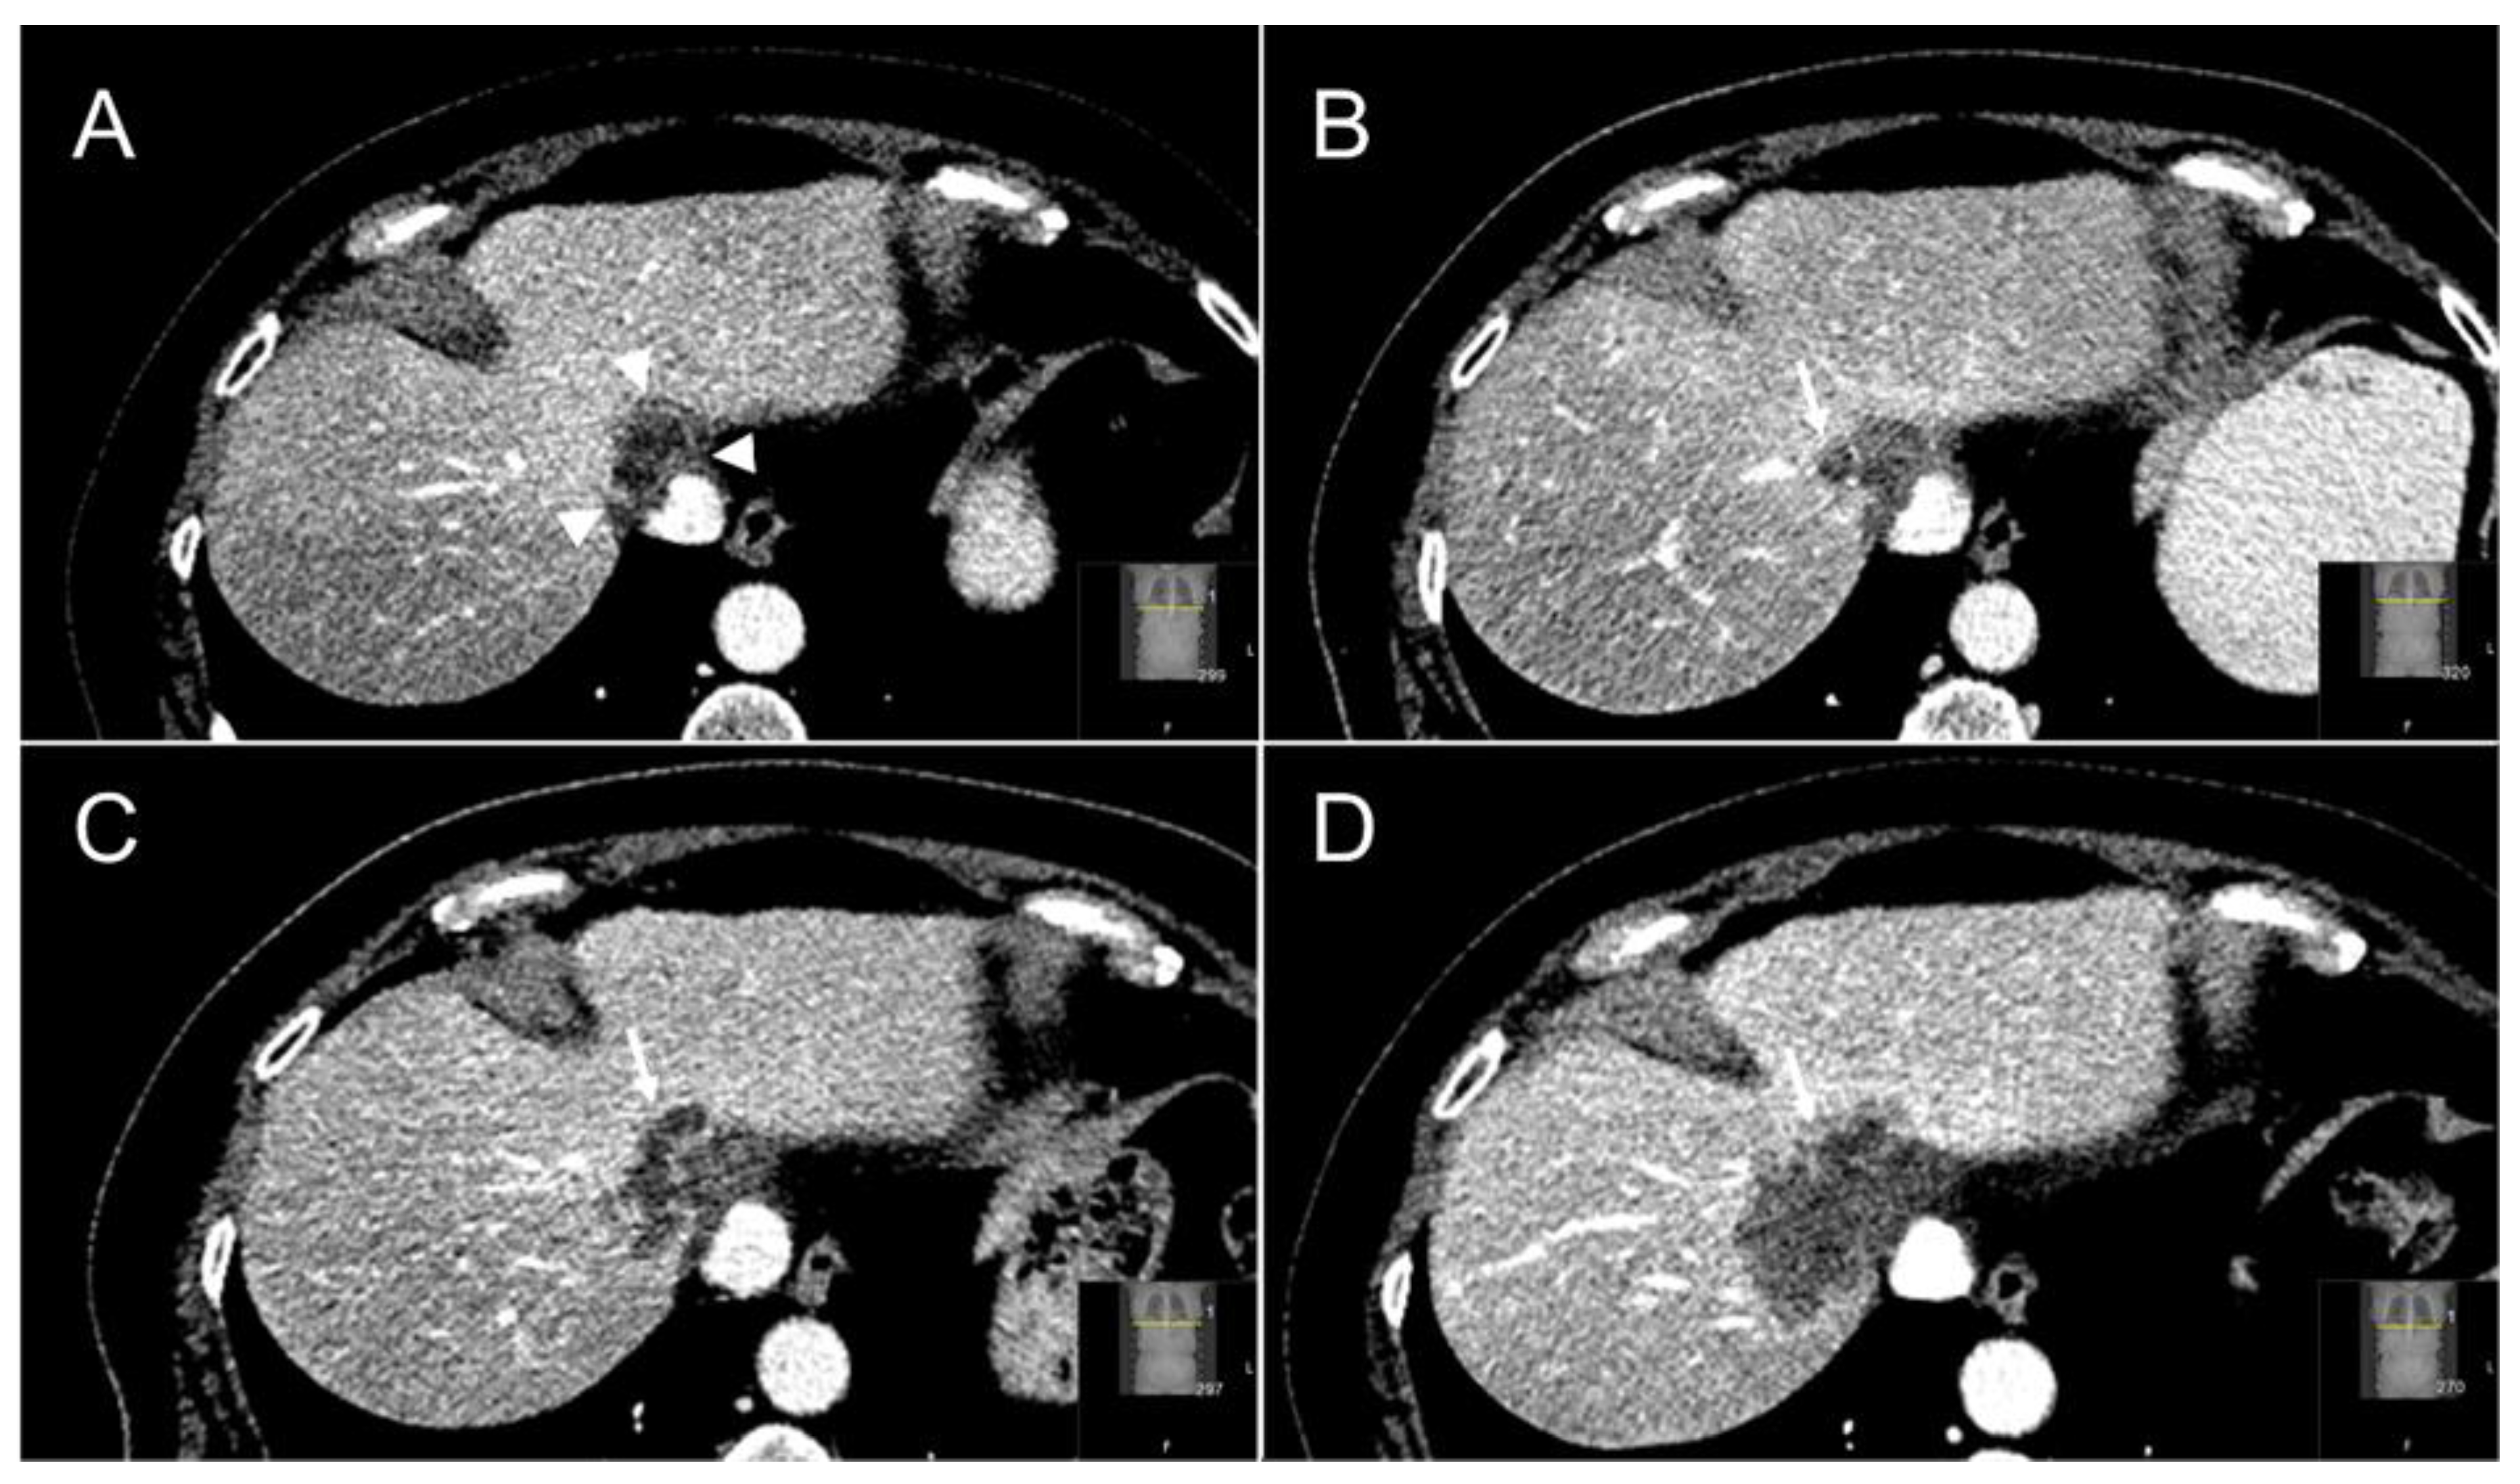

2.5. Follow-Up

- Tetreau, R.; Llacer, C.; Riou, O.; Deshayes, E. Evaluation of response after SBRT for liver tumors. Reports of practical oncology and radiotherapy. J. Greatpoland Cancer Cent. Pozn. Pol. Soc. Radiat. Oncol. 2017, 22, 170–175. [Google Scholar]

- Jarraya, H.; Borde, P.; Mirabel, X.; Ernst, O.; Boulanger, T.; Lartigau, E.; Ceugnart, L.; Kramar, A.; Taieb, S. Lobulated Enhancement Evaluation in the Follow-Up of Liver Metastases Treated by Stereotactic Body Radiation Therapy. Int. J. Radiat. Oncol. 2015, 92, 292–298. [Google Scholar] [CrossRef] [PubMed] [Green Version]

- Yip, C.; Cook, G.J.R.; Owczarczyk, K.; Goh, V. Challenges in imaging assessment following liver stereotactic body radiotherapy: Pitfalls to avoid in clinical practice. Chin. Clin Oncol. 2017, 6 (Suppl. 2), S11. [Google Scholar] [CrossRef] [PubMed] [Green Version]